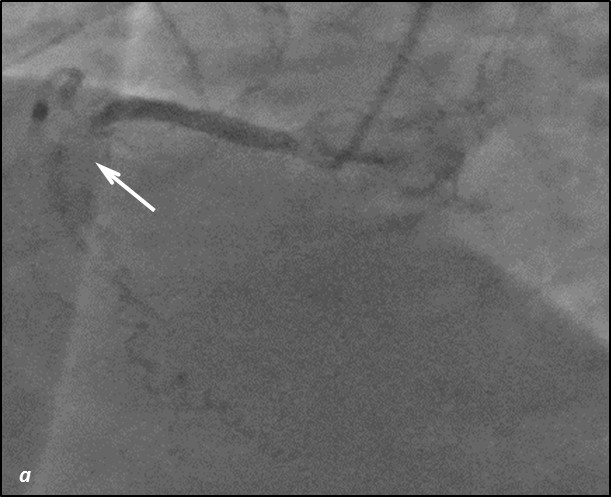

До проведения реваскуляризации миокарда пациент получал двойную антиагрегантную терапию (клопидогрел 75 мг, ацетилсалициловая кислота - 300 мг ежедневно). Чрескожное коронарное вмешательство было разделено на два этапа. Первым этапом – планировалось выполнить реканализацию и стентирование ПМЖВ, вторым – стентирование ПКА. Однако по данным повторной коронарографии было выявлено сужение тела ствола левой коронарной артерии (ЛКА) на 30%, окклюзия от устья передней межжелудочковой артерии (ПМЖВ), постокклюзионный сегмент заполнялся по слабым внутри- и межсистемным коллатералям, устьевое сужение огибающей артерии (ОВ) 60%, окклюзия средней трети правой коронарной артерии (ПКА), постокклюзионный сегмент заполнялся по внутрисистемным перетокам. Показатель Syntax Score для данного пациента составил 34.5. Учитывая, что по данным ранее выполненной коронарографии, правая коронарная артерия оставалась проходимой, а передняя межжелудочковая ветвь была окклюзирована и на момент реваскуляризации срок окклюзии составлял 7 лет, была проведена сменена тактики и первым этапом выполнена реканализация правой коронарной артерии, а спустя 2 суток – реканализация и стентирование передней межжелудочковой ветви от устья с баллонной ангиопластикой огибающей ветви (рис.1,2). Учитывая, что проводилась реканализация хронической окклюзии, в обе коронарные артерии были имплантированы стенты с лекарственным покрытием Resolute ONYX (Medtronic).

Рис.1 Ангиограмма правой корнарной артерии. а) при коронарографии правой коронарной артерии –артерия окклюзирована от уровня п/3 (стрелка); б) проходимость по правой коронарной артерии полностью восстановлена; в) после выполненной реканализации и стентирования ПКА отмечаются межсистемные перетоки в ПМЖВ-ЛКА (стрелка)